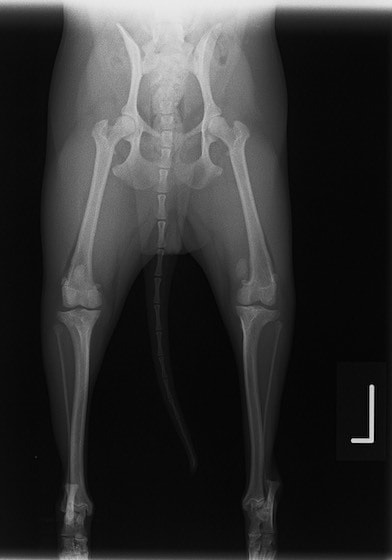

■ 症例24 キャバリア 7か月

左右膝蓋骨内方脱臼(左:グレードⅣ 右:グレードⅢ)

以前から左右後肢の跛行が認められ、整形外科学的検査・レントゲン検査により左右の膝蓋骨脱臼が認められた。症状が重度である左膝の膝蓋骨脱臼整復術を行った。外科手技は縫工筋及び内側広筋の解放、脛骨粗面の外側転位、滑車ブロック形造溝術、内外側関節方の縫縮を実施した。術後一か月時点で、左の膝蓋骨は安定しており経過は良好である。

本症例は成長期における重度の膝蓋骨脱臼であり、術後の再発の可能性もあるため、経過をしっかりと観察していく必要がある。また、今回手術を実施していない右膝に関しても経過を観察し、手術を検討していくこととする。